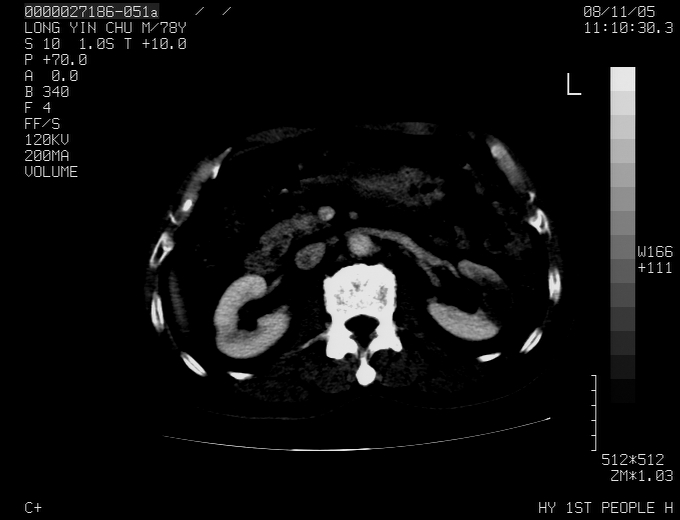

标题: CT16532:M78Y,肝脏病变,请会诊 [打印本页]

标题: CT16532:M78Y,肝脏病变,请会诊

腹胀,腹痛就诊,男性,78岁,外院b超未见异常。

肝ca,脾肾转移

支持脾肾转移瘤,双侧胸腔积液。

考虑弥漫性肝癌并脾及双肾转移.双侧胸水.

图片质量欠佳:多考虑:左侧肾癌。脾脏转移!胸膜转移!

肝脾肾转移瘤可能性大,左肾不除外梗塞,双侧胸水

考虑弥漫性肝癌并脾及双肾转移,双侧胸水。

考虑肝癌并双肾及脾脏转移;双侧胸腔积液。